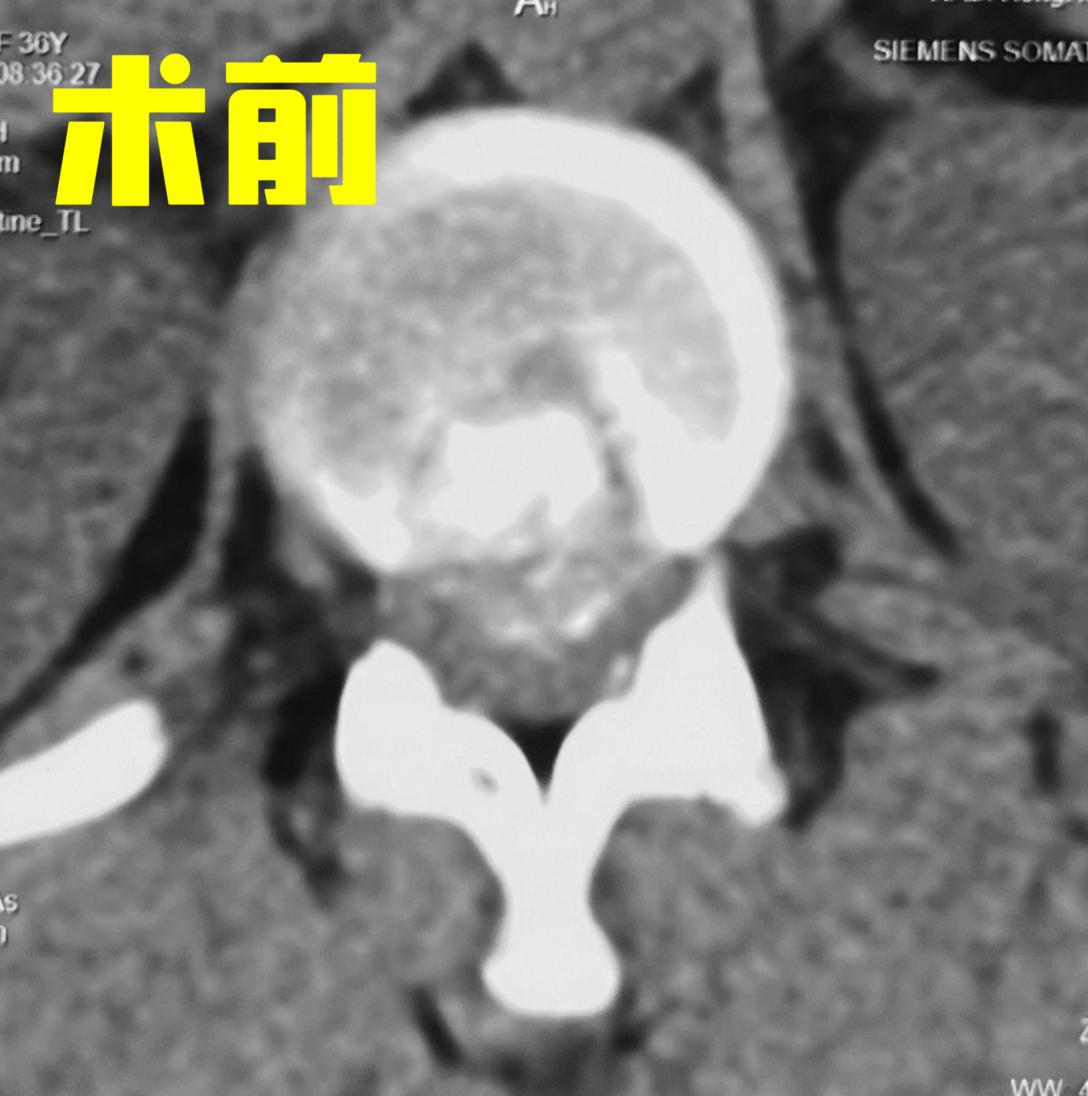

杨俊松副主任医师接诊后结合患者病史、体征和影像学资料指出,患者胸12 腰1椎间盘突出症诊断明确,双侧脊髓神经严重受压,椎间盘严重钙化。

CT显示:间盘突出&钙化严重